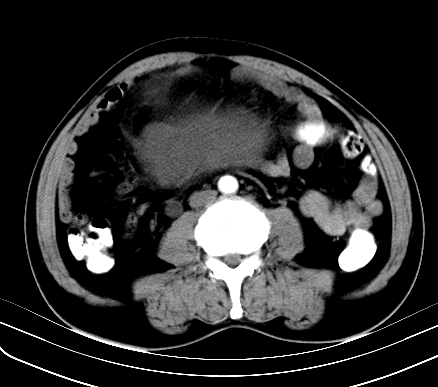

标题: CT19729B:男,74岁,因腿疼就诊,查体触腹部肿物,

增强扫描

动脉期

【ct表现】

1、肿块巨大,往往位于腹膜后,长大后才引起症状而就诊;那么位于腹膜后的肿瘤80%为恶性肿瘤。

2、实性肿瘤,增强扫描轻度不均强化,实性肿瘤一般不是好东西。

3、肿瘤边缘似见少许脂肪样密度。

4、腹膜后未见肿大淋巴结,但肿瘤于临近的肠管及组织接触紧密。

【诊断】

腹部占位,考虑位于腹膜后的恶性肿瘤,脂肪肉瘤(实体型)可能性大。

应该是腹腔病变,病灶较大,内可见脂肪密度影,边界较清,有钻孔样改变,表皮强化,考虑畸胎瘤(皮样囊肿)可能性大.

囊性肿物较大,定位有一定困难,考虑腹腔内肠源性肿瘤或腹膜后间隙囊性肿瘤.性质待定.

术后病理结果:腹膜后脂肪肉瘤。